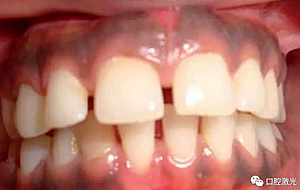

術(shù)后即刻

患者術(shù)后無明顯疼痛不適,沒有出現(xiàn)大量出血、感染或結(jié)痂現(xiàn)象。整個(gè)恢復(fù)過程較為順利?;颊呓邮芏雀撸委熜Ч黠@。